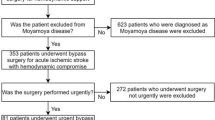

Patient date

A retrospective survey of the 36 cerebral hemispheres of 31 patients who underwent STA-MCA bypass at our institution from July 2021 to August 2022 was conducted. According to the presence or absence of CHS after surgery, CHS and non-CHS groups of patients were separated. One hemisphere (1 patient) had a new cerebral infarction after surgery, and on postoperative CT or MRI scans, none of the remaining patients had cerebral hemorrhage or infarction. Intraoperative hemodynamic characterization was performed using ICG-FLOW800 video angiography in all cases. The Chinese guidelines for the diagnosis and treatment of MMD and moyamoya syndrome developed by the Stroke Prevention Project Committee, National Health and Family Planning Commission, China, were followed by all patients. Prior to surgery, each patient had a magnetic resonance perfusion imaging to confirm areas of hypoperfusion. The study was approved by the Institutional Review Board of Qingdao University Hospital. Informed consent was obtained from the study participants, including legal guardians of minors.